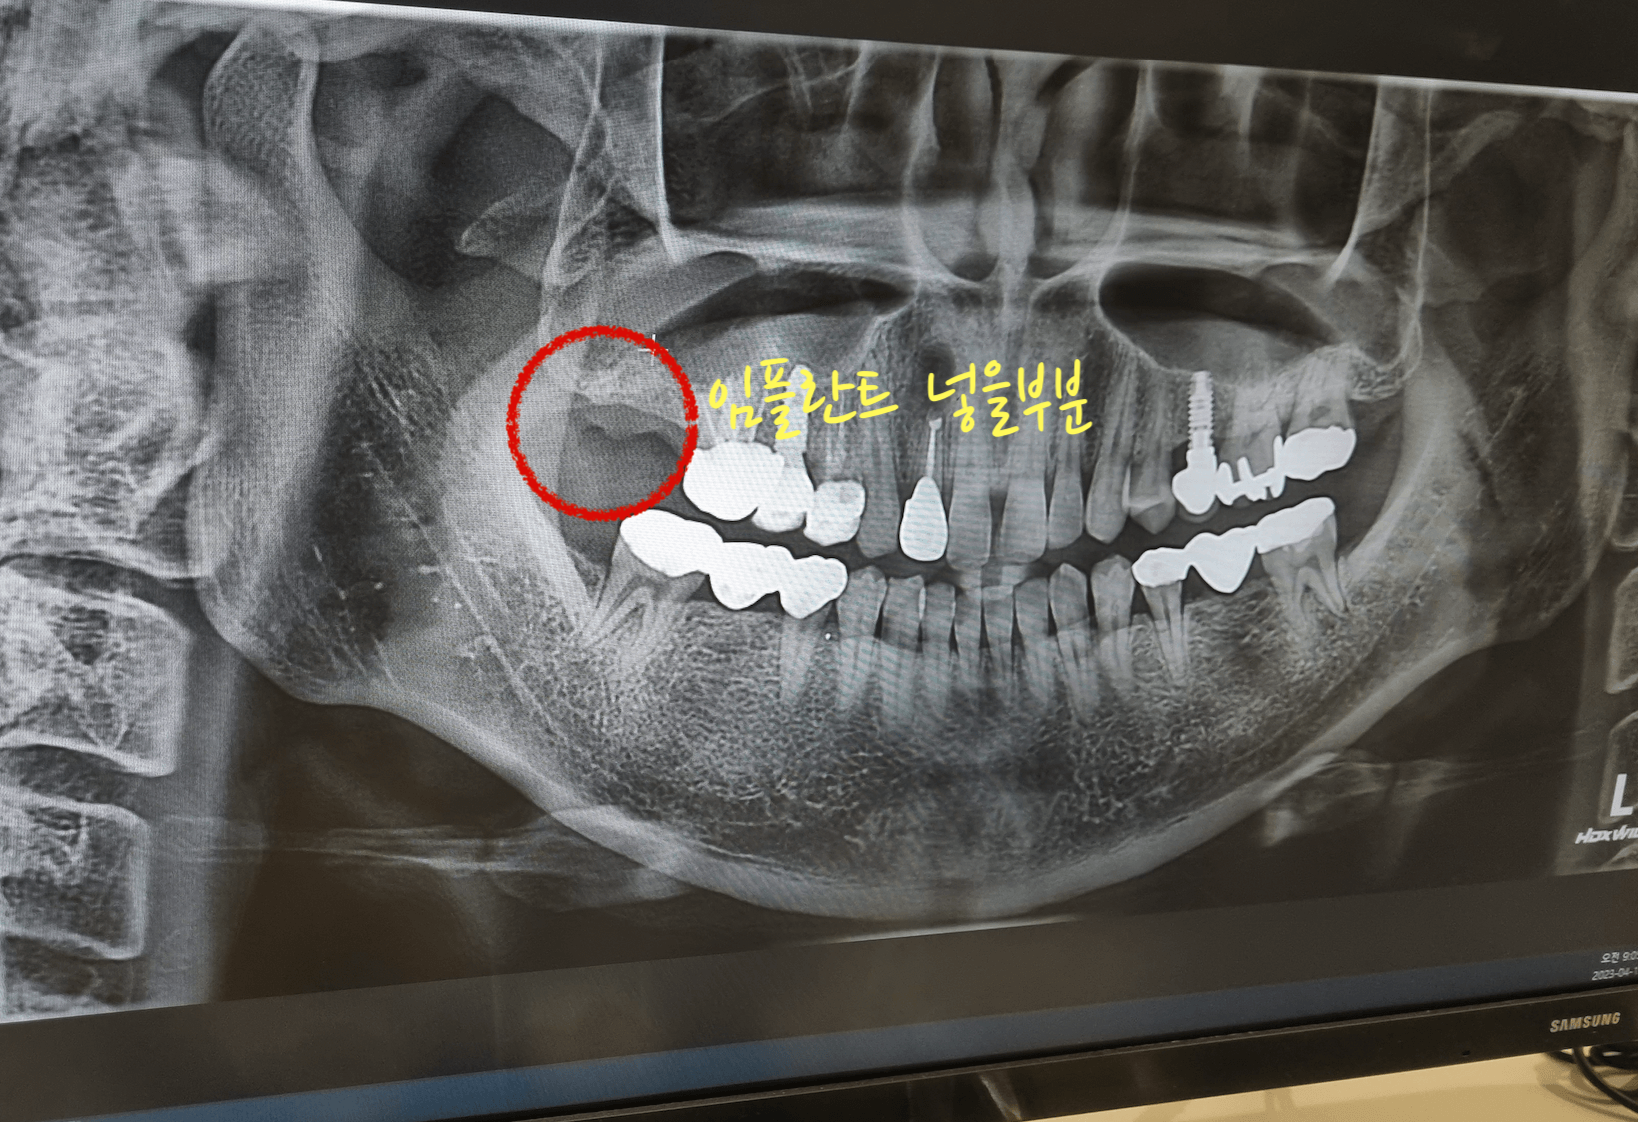

지금 치아 뼈이식 임플란트를 하고 와서 글을 쓰고 있습니다. 요즘 치과도 많은 발전을 해서 임플란트 뼈이식을 하는데 하나도 아프지 않고 시간도 30분 정도로 뼈이식과 지지대를 완성했습니다. 뼈이식 임플란트 비용과 통증에 관한 후기를 남겨 봅니다.

어금니 맨안쪽 치아를 염증 때문에 발치하고 3개월 뒤 어느 정도 뼈가 아물고, 오늘 해당 어금니 부분에 뼈이식과 임플란트 지지대를 삽입하고 왔습니다. 이것까지 하고 나서 치조골 이식한 것과 임플란트가 잘 아물면 그 이후 보철을 씌우면 됩니다.

이번 포스팅의 사진 또한 저의 치아 상태 사진 입니다. 그러니 불법으로 퍼가지 마세요, 부끄럽습니다. 대부분의 치아가 크라운을 씌우거나 임플란트를 해놓은거라 부끄럽네요. 대신 이모든것들이 직접 경험한 내용이기에 팩트는 확실히 전달 될것 같습니다. 아래 포스팅 또한 제가 모두 경험한 내용이니 참고하세요.